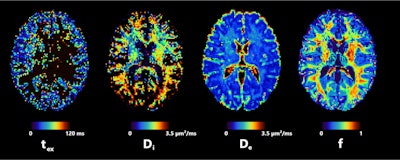

Axial slice of NEXI parametric maps in one subject. The first and third images are consistent throughout the cortex; the first image seems to have more white matter, but this cannot be reliably estimated using available diffusion times. The fourth image displays the expected anatomical pattern in white versus gray matter. The second image shows large variability across voxels while hitting its upper bound frequently. All figures courtesy of Quentin Uhl et al and presented at ISMRM 2023."By quantifying features in the cortex such as neurite density or cell membrane permeability and how they change in pathology, the NEXI model has the potential to enhance our understanding and management of neurological and psychiatric diseases," he said.